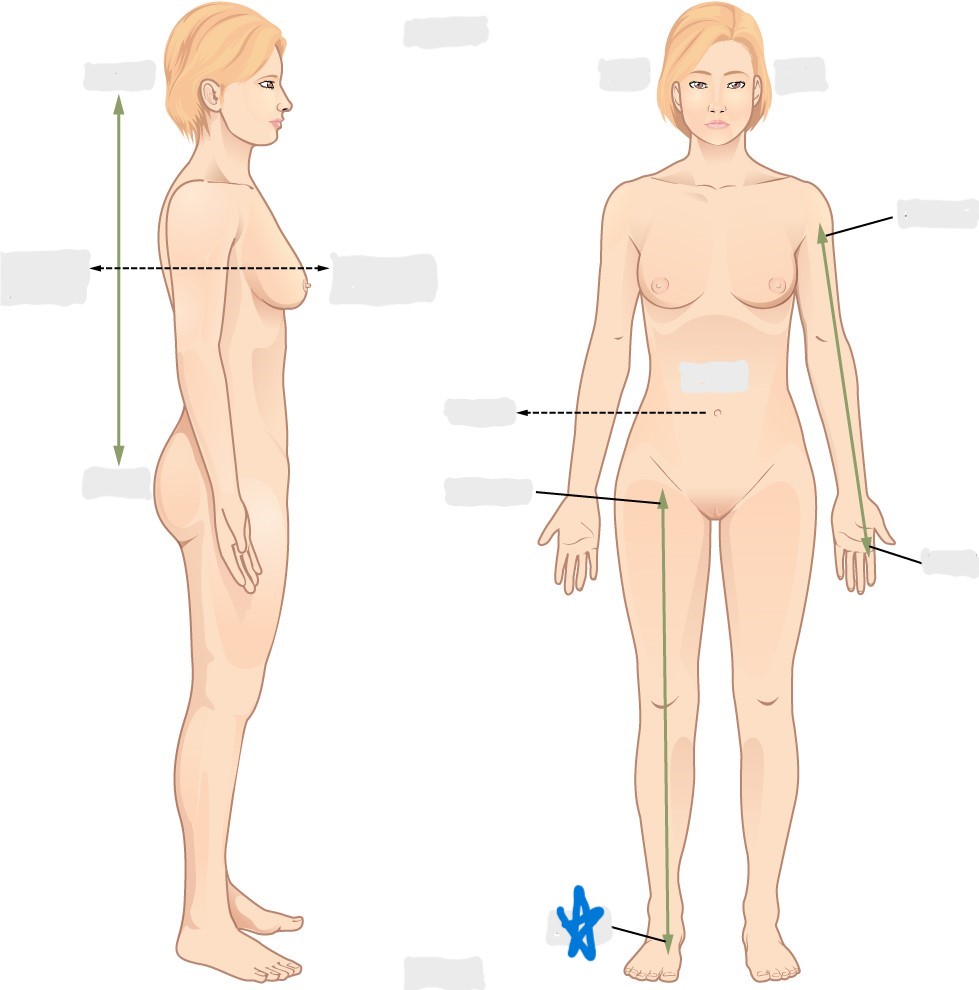

axial

appendicular

acromial

brachial

antecubital

olecranal

antebrachial

carpal

manus

coxal

femoral

patellar

popliteal

crural

sural

peroneal

calcaneal

plantar

sagittal plane

frontal/coronal plane

transverse plane

dorsal/posterior

ventral/anterior

lateral

medial

distal

proximal

superficial

deep

superior

inferior